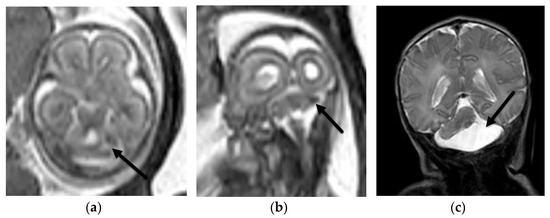

3.1.1. Aqueductal Stenosis

- Heaphy-Henault, K.; Guimaraes, C.; Mehollin-Ray, A.; Cassady, C.I.; Zhang, W.; Desai, N.K.; Paldino, M.J. Congenital aqueductal stenosis: Findings at fetal MRI that accurately predict a postnatal diagnosis. Am. J. Neuroradiol. 2018, 39, 942–948. [Google Scholar] [CrossRef] [PubMed] [Green Version]

- Kline-Fath, B.M.; Arroyo, M.S.; Calvo-Garcia, M.A.; Horn, P.S.; Thomas, C. Prenatal aqueduct stenosis: Association with rhombencephalosynapsis and neonatal outcome. Prenat. Diagn. 2018, 38, 1028–1034. [Google Scholar] [CrossRef] [PubMed]